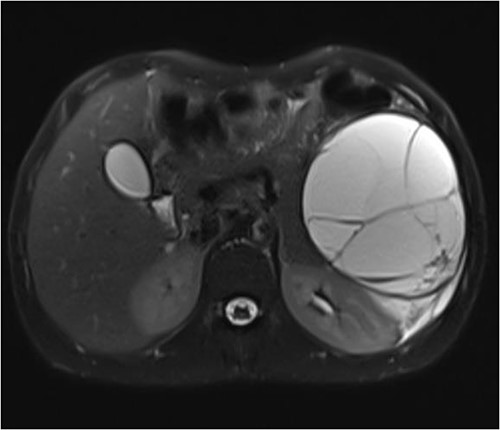

The patient is a 26-year-old male with no chronic medical illnesses who underwent LSG 1 year before his presentation. He presented to the emergency department complaining of intermittent abdominal pain for 4 days. The patient reported feeling fullness in the left upper quadrant area and denied any recent history of abdominal trauma. Examination revealed a swelling at the left upper quadrant. Laboratory investigations were unremarkable. Contrast-enhanced computed tomography showed a large septated cystic lesion of 10 cm compressing the left kidney (Fig. 1). A magnetic resonance image confirmed a non-enhancing cyst with internal septations (Fig. 2). Several factors made us offer laparoscopic exploration and cyst removal to the patient, including the reported symptoms, the cyst size and to confirm the nature of the cyst.

T2 abdominal contrast magnetic resonance image showing the cyst